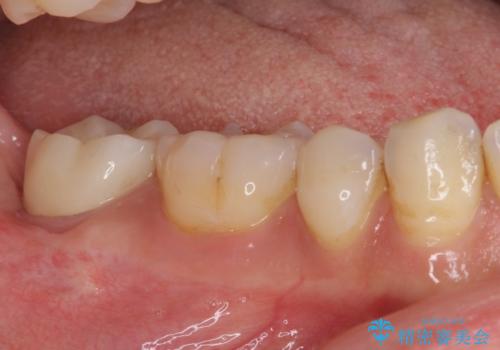

- 根管治療の専門医院で根管治療を行った後、セラミッククラウンによる補綴治療を希望して来院された患者様です。

根管治療後の土台も構築されていたので、仮歯に置き換えた後にフルジルコニアクラウンにて補綴することとしました。

遠心の歯肉が盛り上がっていたため、清掃性が悪くなる懸念がありましたが、クラウン装着による歯肉の腫れは認められませんでした。